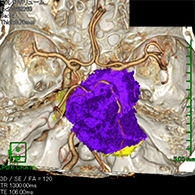

症例1) 65歳男性、頭蓋底部巨大髄膜腫、外科手術のみ

<画像所見>

巨大脳腫瘍を認める。

錐体斜台部巨大髄膜腫を認め、

神経や血管を巻き込んでいる。